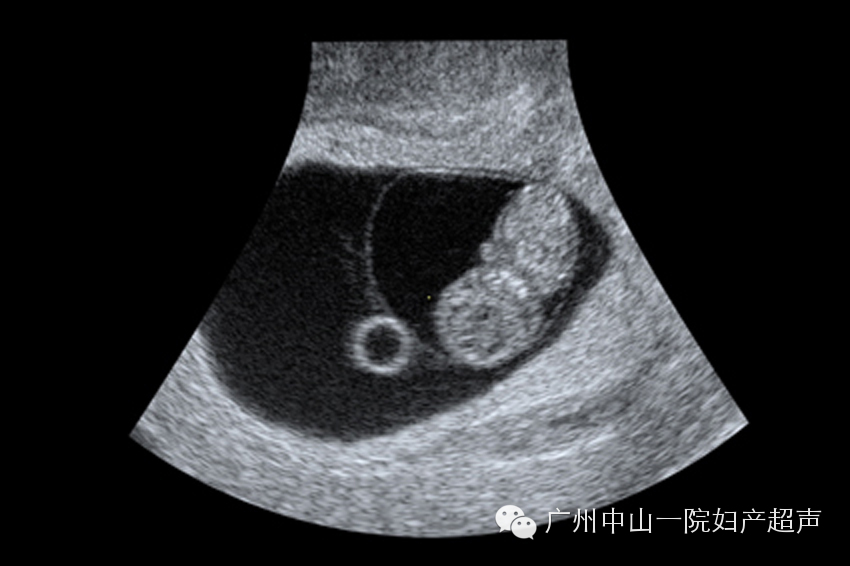

宫内妊娠8周胚胎及卵黄囊声像

此次超声检查可以观察妊娠囊的位置以排除宫外孕,但是某些经期不规律、生化妊娠、宫内妊娠胚胎早期停止发育、早期流产等,上述这些情况都有可能宫内外均检查不到妊娠囊,需要定期观察;此次检查还可以观察妊娠囊数目判断多胎妊娠;此次检查还可以判断胚胎是否存活;还可以测量妊娠囊和胚胎的大小来估算孕周,以测量胚胎大小更为准确,因为胚胎发育就好像马拉松比赛一样,一开始所有的胚胎的发育速度都是近似的,越到晚期差距才逐渐拉开,所以越早期估算的孕周越准确。孕周的判断对于胎儿生长发育的监测是至关重要的,所以对于那些停经时间不明确、月经周期不规律的孕妇来说,这一次超声检查尤其重要。